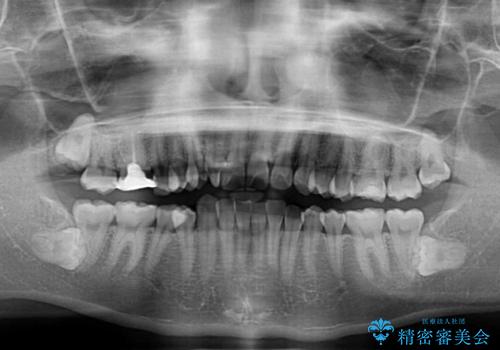

- 前歯のデコボコ、特に90度捻れている上顎前歯を気にして来院された患者様です。

マウスピースでもワイヤーでも対応可能でしたら、捻転が非常に強いことから、患者様と相談の上ワイヤー装置にて矯正治療を行うこととしました。

捻転を解消する際に、歯列全体が前方に突出して出っ歯の仕上がりとなることが懸念されたため、補助装置を用いて上顎歯列全体を後方に移動する力をかけることとしました。

適合や携帯の悪いプラスチックのクラウンが装着されていたため、矯正治療後にオールセラミッククラウンによる補綴治療を行うこととしました。